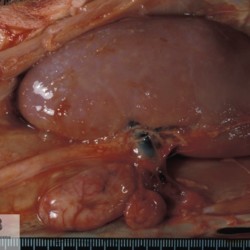

Etiquetes: N-270/92 1 total Porcine Specie: Porcine Organ: Lymph node Lesion: Lymphadenopathy Lesion modifier: - Disease: Porcine circovirosis Files/Expedient: N-270/92 Not viewed Títol Select...Avian (Exotic) (110)Avian (Poultry) (76)Bovine (317)Canine (935)Caprine (47)Equine (257)Feline (326)Ferret (19)General (127)Marine mammal (22)Non-human primate (20)Ovine (328)Porcine (379)Rabbit (61)Reptile (38)Rodent (28)Wildlife (91) Format Select...- (60)Abomasum (37)Adrenal gland (10)Blood (7)Blood vessel (50)Body as a whole (19)Bone (57)Bone marrow (21)Brain (93)Cloaca (1)Diaphragm (2)Ear (5)Esophagus (39)Eye (16)Fetus (12)Gallbladder (23)Gizzard (2)Heart (265)Intestine (356)Joint (32)Kidney (443)Larynx (5)Liver (326)Lung (264)Lymph node (91)Mammary gland (10)Mediastinum (1)Muscle (22)Nasal cavity (22)Nerve (7)Omasum (5)Oral cavity (63)Ovary (14)Oviduct (8)Pancreas (7)Parathyroid (5)Penis (10)Peritoneum (65)Pharynx (9)Pituitary gland (6)Placenta (7)Prostate (8)Proventriculus (3)Reticulum (1)Rumen (28)Sinus (7)Skin (181)Spinal cord (15)Spleen (105)Stomach (125)Teeth (1)Testicle (11)Thoracic cavity (31)Thymus (13)Thyroid gland (5)Tongue (32)Tonsils (11)Trachea (11)Urethra (5)Urinay bladder (61)Uterus (27)Vagina (1)Vulva (1)Yolk sac (1) Cobertura Select...- (152)Abomasitis (26)Abscess (27)Acidosis (1)Adenocarcinoma (20)Adenoma (9)Aerosacculitis (6)Agenesis (1)Agnathia (1)Alopecia (7)Amyloidosis (12)Aneurysm (6)Angiectasis (1)Anthracosis (1)Arteritis (11)Arthritis (15)Arthrogryposis (6)Artifact (4)Ascites (13)Atelectasis (8)Atherosclerosis (5)Atresia (1)Atrial septal defect (2)Atrophy (10)Autolysis (7)Bronchitis (6)Bronchopneumonia (26)Cachexia (2)Carcinoma (103)Cardiomyopathy (19)Cellulitis (2)Chemodectoma (4)Cholangiohepatitis (4)Cholangitis (19)Cholecystitis (4)Cholestasis (5)Chondrodysplasia (2)Chondrosarcoma (2)Chronic passive congestion (13)Chylothorax (2)Cirrhosis (6)Coelomitis (3)Coenurus cerebralis (4)Colitis (40)Congestion (17)Conjunctivitis (5)Coronitis (3)Cryptorchidism (3)Cyst (25)Cystitis (24)Dermatitis (69)Diaphragmatic hernia (4)Dilation (28)Discospondylitis (1)Disseminated intravascular coagulation (7)Dyschondroplasia (1)Dysplasia (29)Ectopia cordis (1)Ectopic ureter (1)Edema (55)Emphysema (5)Encephalitis (5)Endocardiosis (14)Endocarditis (26)Endometritis (5)Enteritis (118)Enterolith (6)Epulis (3)Esophagitis (14)Fasciitis (1)Fibrosis (7)Fibrous osteodystrophy (8)Fistula (1)Folliculitis (3)Fracture (2)Gastritis (34)Gingivitis (5)Glioma (8)Glomerulonephritis (21)Glossitis (25)Glycogenosis (1)Gout (8)Granuloma (2)Granulosa cell tumor (4)Hemangioma (9)Hemangiosarcoma (46)Hematoma (8)Hemoglobinuria (2)Hemopericardium (12)Hemoperitoneum (2)Hemorrhage (100)Hemosiderosis (7)Hemothorax (2)Hepatitis (78)Hernia (11)Histiocytosis (3)Hydatid cyst (11)Hydrocephalus (9)Hydrometra (1)Hydronephrosis (22)Hydropericardium (6)Hydrothorax (3)Hydroureter (5)Hyperkeratosis (8)Hyperostosis (4)Hyperplasia (37)Hypertrophy (9)Hypopigmentation (1)Hypoplasia (7)Hypopyon (1)Impaction (6)Infarction (63)Insulinoma (6)Intussusception (5)Jaundice (17)Laminitis (2)Laryngitis (2)Leiomyoma (5)Leukemia (13)Lipidosis (36)Lipoma (7)Lymphadenitis (45)Lymphadenopathy (7)Lymphangiectasia (6)Lymphangitis (5)Lymphoma (221)Malacia (11)Malignant melanoma (15)Mast cell tumor (11)Mastitis (8)Megaesophagus (2)Melanosis (3)Melena (4)Meningioma (6)Meningitis (6)Meningocele (2)Meningoencephalitis (5)Mesothelioma (5)Methemoglobinemia (2)Mineralization (10)Mucocele (5)Mucometra (1)Multilobular bone tumor (1)Mummification (3)Myelofibrosis (1)Myocarditis (4)Myositis (5)Necrosis (81)Nephritis (113)Nephroblastoma (6)Nephrosclerosis (1)Nephrosis (14)Neuritis (1)Obstruction (13)Omasitis (4)Omphalitis (1)Omphalophlebitis (7)Orchitis (4)Osteoarthrosis (5)Osteomyelitis (9)Otitis (2)Palatoschisis (3)Pancreatitis (3)Panniculitis (3)Papilloma (7)Parakeratosis (14)Patent ductus arteriosus (6)Peliosis hepatis (1)Perforation (17)Pericarditis (35)Peritonitis (39)Persistent right aortic arch (1)Pharyngitis (2)Pheochromocytoma (2)Phlebitis (2)Placentitis (6)Pleuritis (21)Pleuropneumonia (24)Pneumonia (109)Pneumothorax (3)Polycystosis (14)Polyp (5)Polyserositis (6)Posthitis (1)Proctitis (4)Prolapse (3)Prostatitis (3)Proventriculitis (1)Pyelonephritis (24)Pyometra (6)Pyothorax (4)Rhinitis (11)Rumenitis (6)Rupture (24)Salpingitis (3)Sarcoma (57)Sclerosis (1)Scoliosis (2)Seminoma (2)Sequestrum (2)Serous atrophy (14)Sinusitis (7)Splenitis (14)Splenomegaly (9)Spondylitis (6)Spondylosis (1)Stenosis (9)Stomatitis (32)Tenosynovitis (2)Teratoma (3)Thricobezoar (2)Thrombosis (16)Tonsilitis (4)Torsion (13)Tracheitis (4)Tympany (7)Typhlitis (8)Typhlocolitis (4)Ulcer (43)Urethritis (1)Urolithiasis (36)Uroperitoneum (1)Uveitis (1)Vasculitis (15)Ventricular septal defect (3)Volvulus (11) Matèria Select... - (14)- (1653)- (152)Abomasitis - Catarrhal (2)Abomasitis - Catarrhal-hemorrhagic (1)Abomasitis - Chronic (1)Abomasitis - Fibrinous-necrotizing (2)Abomasitis - Hyperplasic (5)Abomasitis - Hyperplasic - Chronic (1)Abomasitis - Necrotic (1)Abomasitis - Necrotizing (2)Abomasitis - Ulcerative (5)Adenocarcinoma (9)Aerosacculitis - Granulomatous (1)Amyloidosis - Chronic (1)Arteritis - Necrotic (2)Arteritis - Necrotizing (1)Arthritis - Chronic (4)Arthritis - Fibrinous-purulent (3)Arthritis - Serous (4)Arthritis - Subacute (1)Ascites - Serous (1)Atrophy - Serous (1)Bronchitis - Catarrhal (3)Bronchitis - Suppurative (1)Bronchopneumonia - Catarrhal-purulent (17)Bronchopneumonia - Fibrinous (1)Bronchopneumonia - Granulomatous (1)Bronchopneumonia - Purulent (1)Bronchopneumonia - Suppurative (5)Carcinoma - Adenocarcinoma (33)Carcinoma - Adenocarcinoma - Hepatocellular (2)Carcinoma - Adenocarcinoma - Mucinous (1)Carcinoma - Basosquamous (1)Carcinoma - Cholangiocellular (3)Carcinoma - Hepatocellular (4)Carcinoma - Metastatic (3)Carcinoma - Squamous cell carcinoma (13)Carcinoma - Transitional cell (2)Cardiomyopathy - Dilated (13)Cardiomyopathy - Hypertrophic (6)Cellulitis - Necrotizing (1)Cholangitis - Chronic (8)Cholangitis - Hyperplasic (3)Cholecystitis - Fibrinous-necrotizing (1)Coelomitis - Fibrinous (1)Coelomitis - Granulomatous (1)Colitis - Catarrhal (3)Colitis - Catarrhal-hemorrhagic (1)Colitis - Fibrinous (1)Colitis - Fibrinous-necrotizing (1)Colitis - Fibrinous-necrotizing (Diphtheritic) (6)Colitis - Granulomatous (2)Colitis - Hemorrhagic (4)Colitis - Hemorrhagic-necrotizing (3)Colitis - Necrotizing (2)Colitis - Ulcerative (6)Congestion - Chronic (2)Conjunctivitis - Hyperplasic (1)Conjunctivitis - Purulent (3)Coronitis - Ulcerative (1)Cystitis - Chronic (3)Cystitis - Fibrinous (1)Cystitis - Fibrinous-necrotizing (1)Cystitis - Follicular (1)Cystitis - Hemorrhagic (6)Cystitis - Hemorrhagic-ulcerative (1)Cystitis - Necrotizing (9)Cystitis - Perforated (1)Dermatitis - Granulomatous (14)Dermatitis - Hyperkeratotic (10)Dermatitis - Hyperplasic (proliferative) (1)Dermatitis - Hyperplastic (10)Dermatitis - Necrotizing (4)Dermatitis - Pustular (4)Dermatitis - Ulcerative (2)Dilation - Chronic (1)Discospondylitis - Necrotizing (1)Dysplasia - Follicular (5)Edema - Interstitial (6)Emphysema - Interstitial (1)Encephalitis - Granulomatous (1)Encephalitis - Nonsuppurative (1)Endocardiosis - Mitral (7)Endocardiosis - Mitral - Chronic (5)Endocarditis - Valvular (6)Endocarditis - Valvular - Mitral (7)Endocarditis - Valvular - Pulmonic (1)Endocarditis - Valvular - Subacute (1)Endocarditis - Valvular - Subaortic (5)Endocarditis - Valvular - Tricuspid (4)Endometritis - Purulent (3)Endometritis - Purulent-hemorrhagic (2)Enteritis - Catarrhal (23)Enteritis - Catarrhal - Acute (1)Enteritis - Catarrhal-hemorrhagic (5)Enteritis - Catarrhal-hemorrhagic - Acute (2)Enteritis - Fibrinous (16)Enteritis - Fibrinous - Acute (3)Enteritis - Fibrinous-necrotizing (7)Enteritis - Granulomatous (14)Enteritis - Granulomatous - Chronic (1)Enteritis - Granulomatous - Multifocal (1)Enteritis - Hemorrhagic (17)Enteritis - Hemorrhagic - Acute (1)Enteritis - Hemorrhagic-necrotizing (1)Enteritis - Hyperplasic (proliferative) (4)Enteritis - Necrotizing (4)Enteritis - Necrotizing - Acute (1)Enteritis - Necrotizing - Hemorrhagic (1)Enteritis - Necrotizing-ulcerative (2)Enteritis - Ulcerative (1)Enteritis - Ulcerative-hemorrhagic (1)Esophagitis - Erosive-ulcerative (6)Esophagitis - Necrotizing (4)Esophagitis - Ulcerative (1)Esophagitis - Ulcerative-necrotizing (1)Fasciitis - Fibrinous-purulent (1)Folliculitis - Purulent (2)Gastritis - Catarrhal (2)Gastritis - Chronic (1)Gastritis - Follicular (1)Gastritis - Hemorrhagic (2)Gastritis - Hemorrhagic-necrotizing (1)Gastritis - Hypertrophic (2)Gastritis - Inclusion bodies (1)Gastritis - Mineralization (1)Gastritis - Mycotic (1)Gastritis - Necrotizing (2)Gastritis - Ulcerative (6)Gastritis - Uremic (3)Gingivitis - Erosive (2)Gingivitis - Hyperplasic (proliferative) (1)Gingivitis - Necrotizing (1)Glomerulonephritis - Chronic (7)Glomerulonephritis - Membranoproliferative (3)Glomerulonephritis - Membranoproliferative - Chronic (1)Glomerulonephritis - Membranous (3)Glomerulonephritis - Membranous - Chronic (1)Glomerulonephritis - Proliferative (2)Glomerulonephritis - Subacute (1)Glossitis - Erosive (2)Glossitis - Granulomatous (6)Glossitis - Hyperplasic (1)Glossitis - Hyperplasic (proliferative) (2)Glossitis - Hyperplastic (1)Glossitis - Necrotizing (2)Glossitis - Necrotizing - Focal (1)Glossitis - Ulcerative (6)Glossitis - Ulcerative - Multifocal (1)Glossitis - Ulcerative - Subacute (1)Glycogenosis (1)Granuloma - Eosinophilic (1)Hemangiosarcoma - Metastatic (2)Hemorrhage - Acute (1)Hemorrhage - Subcapsular (3)Hepatitis - Abscess (9)Hepatitis - Acute (3)Hepatitis - Chronic (4)Hepatitis - Chronic interstitial (6)Hepatitis - Granulomatous (7)Hepatitis - Interstitial - Multifocal (1)Hepatitis - Interstitial - Subacute (1)Hepatitis - Necrotizing (17)Hepatitis - Necrotizing - Acute (2)Hepatitis - Necrotizing - Hemorrhagic (1)Hepatitis - Necrotizing - Subacute (1)Hepatitis - Pyogranulomatous (7)Hepatitis - Subacute (4)Hydronephrosis - Chronic (1)Hydropericardium - Chronic (1)Hyperplasia - Erythroid (1)Hyperplasia - Lymphoid (3)Hyperplasia - Myeloid (1)Hyperplasia - Nodular (8)Hypertrophy - Concentric (2)Hypertrophy - Eccentric (3)Infarction - Acute (17)Infarction - Acute - Multifocal (2)Infarction - Chronic (5)Infarction - Chronic - Multifocal (1)Infarction - Subacute (18)Infarction - Subacute - Focal (2)Laminitis - Chronic (2)Laryngitis - Necrotic (1)Laryngitis - Necrotizing (1)Leukemia - Lymphoid leukemia (2)Leukemia - Non-lymphoid leukemia (6)Lipidosis - Multifocal (1)Lipidosis - Panlobular (1)Lipidosis - Panlobular - Generalized (2)Lymphadenitis - Granulomatous (24)Lymphadenitis - Granulomatous - Chronic (3)Lymphadenitis - Hemorrhagic (1)Lymphadenitis - Necrotizing (5)Lymphadenitis - Necrotizing (caseous) (11)Lymphangitis - Granulomatous (1)Lymphangitis - Purulent (1)Lymphangitis - Ulcerative (1)Lymphoma - Alimentary lymphoma (7)Lymphoma - Cutaneous lymphoma (6)Lymphoma - Lymphosarcoma (2)Lymphoma - Mediastinal lymphoma (1)Lymphoma - Multicentric lymphoma (29)Malignant melanoma - Malignant (1)Malignant melanoma - Metastatic (1)Mast cell tumor - Metastatic (1)Mastitis - Fibrinous-purulent (2)Mastitis - Necrotic (1)Mastitis - Purulent (3)Mastitis - Suppurative (1)Meningitis - Fibrinous-purulent (2)Meningitis - Purulent (4)Meningoencephalitis - Necrotizing (3)Meningoencephalitis - Nonsuppurative (2)Mineralization - Metastatic (4)Myocarditis - Fibrous - Chronic (1)Myocarditis - Granulomatous (1)Myositis - Purulent (2)Necrosis - Acute (1)Necrosis - Cortical (5)Necrosis - Follicular (1)Necrosis - Papillary (8)Necrosis - Papillary - Acute (3)Necrosis - Subacute (3)Necrosis - Tubular (6)Nephritis - Embolic (2)Nephritis - Embolic suppurative (7)Nephritis - Granulomatous (27)Nephritis - Granulomatous - Chronic (1)Nephritis - Granulomatous - Multifocal (1)Nephritis - Interstitial (6)Nephritis - Interstitial - Acute (4)Nephritis - Interstitial - Chronic (41)Nephritis - Interstitial - Subacute (12)Nephritis - Purulent (7)Nephritis - Purulent - Acute (2)Nephritis - Purulent - Multifocal (3)Nephrosis - Cholemic (3)Nephrosis - Hemoglobinuric (10)Omasitis - Fibrinous-necrotizing (1)Omasitis - Hyperkeratotic (1)Omasitis - Necrotizing (2)Omphalophlebitis - Fibrinous-purulent (2)Omphalophlebitis - Purulent (3)Orchitis - Necrotizing (1)Osteomyelitis - Necrotizing (7)Osteomyelitis - Purulent (2)Otitis - Necrotizing (1)Otitis - Proliferative (1)Pancreatitis - Acute (1)Pancreatitis - Chronic (1)Pancreatitis - Granulomatous (1)Panniculitis - Fibrinous-purulent (1)Panniculitis - Necrotic (1)Panniculitis - Parasitic (1)Perforation - Acute (2)Pericarditis - Fibrinous (19)Pericarditis - Fibrinous - Subacute (1)Pericarditis - Fibrinous-necrotizing (1)Pericarditis - Fibrinous-purulent (3)Pericarditis - Fibrous (1)Pericarditis - Fibrous - Chronic (1)Pericarditis - Gangrenous (6)Pericarditis - Granulomatous (1)Pericarditis - Granulomatous - Chronic (2)Peritonitis - Acute (1)Peritonitis - Fibrinous (11)Peritonitis - Fibrinous - Subacute (1)Peritonitis - Fibrinous-purulent (5)Peritonitis - Fibrous (3)Peritonitis - Granulomatous (6)Peritonitis - Purulent (1)Peritonitis - Purulent-hemorrhagic (1)Peritonitis - Pyogranulomatous (3)Pharyngitis - Fibrinous-necrotizing (1)Pharyngitis - Ulcerative (1)Pheochromocytoma - Metastatic (1)Phlebitis - Purulent (1)Placentitis - Fibrinous-necrotizing (1)Placentitis - Necrotic (1)Placentitis - Necrotizing (1)Pleuritis - Chronic (1)Pleuritis - Fibrinous (3)Pleuritis - Fibrinous-purulent (2)Pleuritis - Fibrous (2)Pleuritis - Granulomatous (3)Pleuritis - Hyperplastic (2)Pleuritis - Purulent (2)Pleuritis - Pyogranulomatous (1)Pleuropneumonia - Fibrinous (13)Pleuropneumonia - Fibrinous-necrotizing (5)Pleuropneumonia - Granulomatous (2)Pleuropneumonia - Hemorrhagic-necrotizing (4)Pneumonia - Aspiration (11)Pneumonia - Bronchointerstitial (4)Pneumonia - Bronchointerstitial - Subacute (1)Pneumonia - Embolic (5)Pneumonia - Granulomatous (37)Pneumonia - Granulomatous - Multifocal (4)Pneumonia - Hemorrhagic-necrotizing (2)Pneumonia - Interstitial (7)Pneumonia - Interstitial - Acute (8)Pneumonia - Interstitial - Chronic (6)Pneumonia - Interstitial - Subacute (15)Pneumonia - Necrotizing (2)Pneumonia - Pyogranulomatous (2)Pneumonia - Verminous (5)Polyserositis - Fibrinous (6)Polyserositis - Fibrous (1)Proctitis - Fibrinous-necrotizing (1)Proctitis - Parasitic (2)Prostatitis - Purulent (1)Pyelonephritis - Acute (2)Pyelonephritis - Chronic (3)Rhinitis - Catarrhal (2)Rhinitis - Fibrinous (1)Rhinitis - Granulomatous (4)Rhinitis - Purulent (3)Rumenitis - Acute (1)Rumenitis - Erosive (1)Rumenitis - Necrotizing (1)Rupture - Acute (3)Sarcoma - Fibrosarcoma (12)Sarcoma - Hemangiosarcoma (11)Sarcoma - Histiocytic (7)Sarcoma - Metastatic (1)Sarcoma - Multilobular tumor of bone (1)Sequestrum - Chronic (2)Sinusitis - Suppurative (1)Splenitis - Granulomatous (8)Splenitis - Granulomatous - Chronic (1)Splenitis - Necrotizing (3)Splenitis - Necrotizing (caseous) (2)Spondylitis - Necrotizing (2)Stenosis - Intestinal (1)Stenosis - Valvular - Subaortic (4)Stomatitis - Erosive (12)Stomatitis - Erosive-ulcerative (3)Stomatitis - Fibrinous-necrotizing (1)Stomatitis - Fibrinous-necrotizing (Diphtheritic) (1)Stomatitis - Granulomatous (1)Stomatitis - Hyperplasic (1)Stomatitis - Hyperplasic (proliferative) (1)Stomatitis - Necrotizing (2)Stomatitis - Ulcerative (5)Stomatitis - Ulcerative - Multifocal (1)Stomatitis - Ulcerative-necrotizing (1)Tonsilitis - Necrotizing (4)Torsion - Acute passive hyperemia (5)Tracheitis - Catarrhal (3)Tracheitis - Fibrinous (1)Tracheitis - Granulomatous (1)Typhlitis - Catarrhal (1)Typhlitis - Fibrinous-necrotizing (2)Typhlitis - Hemorrhagic (2)Typhlitis - Ulcerative-hemorrhagic (1)Typhlocolitis - Fibrinous-necrotizing (2)Typhlocolitis - Proliferative (1)Ulcer - Chronic (6)Ulcer - Multifocal (2)Ulcer - Mycotic (1)Ulcer - Perforated (6)Urethritis - Hemorrhagic (1)Urolithiasis - Chronic (2)Uveitis - Granulomatous (1)Vasculitis - Granulomatous (1)Vasculitis - Necrotizing (1) Editor Select...- (1970)Acidosis (2)Actinobacillosis (Pleuropneumonia) (11)Aelurostrongylosis (2)African horse sickness (13)African swine fever (14)Alopecia X (1)Anaplasmosis (4)Anthrax (2)Aortic thromboembolism (feline) (7)Ascariasis (15)Aspergillosis (18)Atopic dermatitis (1)Atrophic rhinitis (3)Babesiosis (6)Blackhead (1)Bluetongue (11)Border disease (2)Bovine viral diarrhea (21)Brucellosis (2)Candidiasis (5)Canine distemper (14)Caprine arthritis-encephalitis (2)Capture myopathy (1)Cardiac insufficiency (17)Caseous lymphadenitis (7)Chlamydiosis (2)Classical swine fever (19)Clostridiosis (19)Coccidiosis (9)Coenurosis (4)Colibacillosis (21)Contagious ecthyma (7)Copper toxicosis (11)Cowdriosis (Heartwater) (3)Cryptococcosis (3)Cryptosporidiosis (2)Cysticercosis (23)Demodicosis (1)Diabetes (1)Dicrocoeliosis (5)Dictyocaulosis (4)Dirofilariasis (7)Discoid lupus erythematosus (3)Echinococcosis (17)Edema disease (7)Egg drop syndrome (1)Encephalitozoonosis (5)Enterotoxemia (1)Enzootic bovine leukosis (46)Epitheliogenesis imperfecta (3)Equine rhinopneumonitis (2)Equine verminous arteritis (strongylosis) (7)Erysipelas (5)Exudative epidermitis (7)Fasciolasis (11)Feline eosinophilic dermatoses (1)Feline hepatic lipidosis (8)Feline histiocytosis (4)Feline infectious peritonitis (38)Feline leukemia (4)Feline lower urinary tract disease (3)Feline panleukopenia (16)Feline viral rhinotracheitis (1)Flea allergy dermatitis (1)Foot and mouth disease (2)Gasterophilosis (4)Glasser's disease (15)Gousiekte (4)Gout (6)Haemonchosis (9)Hemolytic anemia (4)Hemorrhagic diathesis (1)Hepatic insufficiency (11)Hepatosis dietetica (7)Herpesvirosis (6)Hyperadrenocorticism (7)Hyperparathyroidism (10)Hypertrophic osteopathy (6)Hypervitaminosis D (1)Hypodermosis (1)Inclusion body hepatitis (4)Infectious bovine rhinotracheitis (5)Infectious bronchitis (5)Infectious canine hepatitis (13)Influenza (4)Juvenile nephropathy (8)Lamb dysentery (4)Leishmaniasis (28)Leptospirosis (1)Leukosis (5)Listeriosis (4)Lumpy skin disease (3)Maedi-visna (4)Malignant catarrhal fever (12)Mange (6)Mannheimiosis (5)Marek's disease (7)Metabolic bone disease (2)Mucoid enteropathy (5)Mulberry heart disease (5)Myasis (1)Mycobacteriosis (22)Mycosis fungoides (6)Myxomatosis (3)Necrobacillosis (5)Neonatal isoerythrolysis (6)Nocardiosis (4)Oestrosis (2)Onchocerciasis (1)Osteochondrosis (1)Ostertagiosis (6)Ovine pulmonary adenocarcinoma (5)Oxyuriasis (1)Pacheco's disease (4)Papillomatosis (6)Paratuberculosis (18)Parvovirosis (17)Pasteurellosis (11)Pemphigus foliaceus (1)Periodontal disease (1)Polioencephalomalacia of ruminants (4)Polyarteritis nodosa (3)Polycystic kidney disease (13)Porcine circovirosis (11)Porcine dermatitis and nephropathy syndrome (9)Porcine proliferative enteropathy (4)Porcine reproductive and respiratory syndrome (6)Porcine stress syndrome (1)Pox (13)Pregnancy toxemia (3)Proventricular dilatation disease (2)Pseudotuberculosis (yersiniosis) (2)Psittacine beak and feather disease (PBFD) (5)Pyoderma (4)Q fever (4)Rabbit hemorrhagic disease (2)Renal insufficiency (12)Reticuloendotheliosis (2)Rhodococcosis (1)Rickets (1)Rinderpest (2)Salmonellosis (34)Sarcosporidiosis (2)Schmallenberg (7)Septicemia (23)Spirocercosis (11)Streptococcosis (5)Strongylosis (1)Swine dysentery (5)Systemic coronavirosis (5)Tetralogy of Fallot (5)Theileriosis (13)Thromboembolism (5)Toxoplasmosis (11)Transmissible viral proventriculitis (1)Traumatic reticuloperitonitis (3)Traumatism (16)Tuberculosis (58)Ulcerative lymphangitis (1)Uremic syndrome (20)Viral arthritis (6)White muscle disease (9)Wobbler syndrome (2)Xanthomatosis (1)Zygomycosis (4) Idioma Select...- (1180)Bacterial (501)Degeneration (106)Fungal (46)Hemodynamic (112)Idiopathic (22)Inflammation (58)Malformation (88)Neoplasia (343)Nutritional (41)Parasitic (243)Physical/Chemical (93)Toxic (44)Viral (304) Ítem destacat Porcine Sow. Porcine Ulcerative Dermatitis Syndrome (PUDS). Interface dermatitis. Lesions were neither painful nor pruritic. University of Pretoria, South…